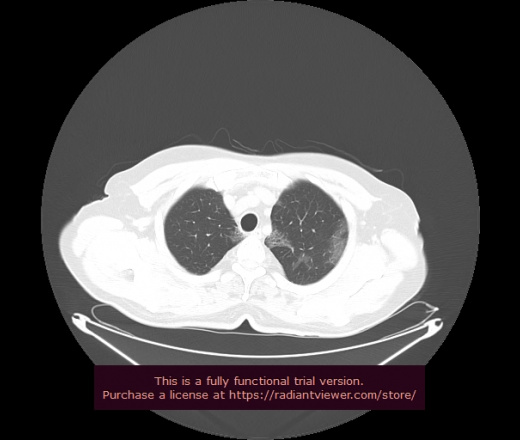

Уважаемые коллеги, если имеется интерес, сможете ли Вы спрогнозировать дальнейшее +-одинаковое течение процесса у 4 данных разных пациентов? Зацепиться где-то можно очень просто, где-то нельзя.